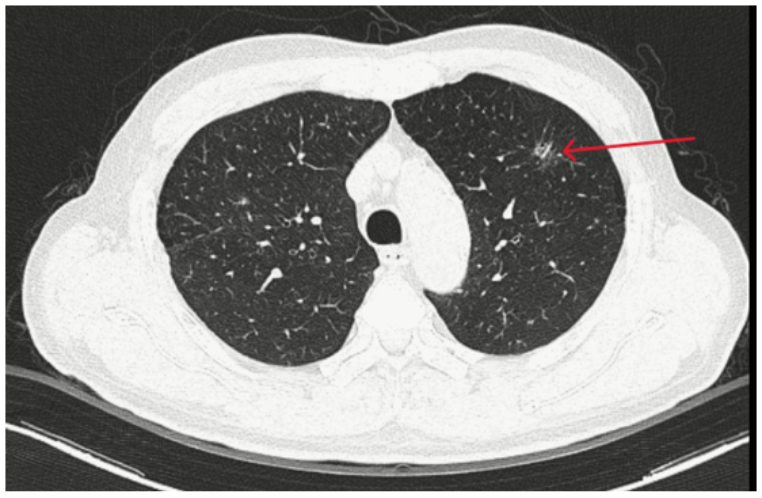

Trong quá trình kiểm tra sau điều trị, bệnh nhân được chụp CT ngực và phát hiện một khối u ở thùy trên phổi trái. Sau đó, ông T. được chuyển đến Trung tâm Y học hạt nhân và Ung bướu - Bệnh viện Bạch Mai để tiếp tục đánh giá và điều trị.

Ông T. có tiền sử hút thuốc lá khoảng 20 bao/năm và mắc tăng huyết áp. Kết quả chụp CT ngực cho thấy một đám tổn thương dạng kính mờ, bờ tua gai ở thùy trên phổi trái là một đặc điểm gợi ý khả năng ác tính.

Tổn thương phổi trên phim CT này tiếp tục được phân tích bằng hệ thống trí tuệ nhân tạo (AI). Kết quả cho thấy xác suất nốt kính mờ ở thùy trên phổi trái là tổn thương ác tính lên tới khoảng 97%. Sau khi hội chẩn đa chuyên khoa, bệnh nhân được chỉ định phẫu thuật.

Hình ảnh CT phổi của ông T. có đám mờ. Ảnh: BSCC.